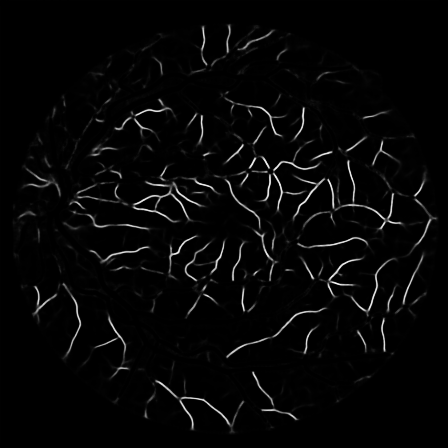

Fig. 2: An example from the DRIVE dataset. Stratification (first row, left to right): (1) input image, (2) raw mask, (3) stem mask, (4) thin mask; Segmentation Results (second row): (5) overall prediction (red are false positive area while green are false negative area), (6) raw prediction, (7) stem prediction, (8) thin prediction (of the Ngsubscript𝑁𝑔N_{g} stream)

To justify the performance of our model, we compare the 4 metrics with 8 representative previous works from all 3 open-access datasets. The comparison results presented in Table 1 show that our MP-Net model outperforms the state-of-the-art methods regarding accuracy and AUC𝐴𝑈𝐶AUC in all three datasets, which meter the practical prediction quality and the overall prediction quality independent on thresholding specifications. The AUC𝐴𝑈𝐶AUC advancement is greater in the DRIVE dataset. It’s related to the fact that the DRIVE dataset contains more thin vessels, which is the main target of our model. Specificity is also the highest in DRIVE and CHASE_DB1 while sensitivity is highest in STARE. Particularly, our method outperforms ML-UNet [2] and JL-UNet [4] which adopt a different multi-class approach to also especially tackle the thin-vessels challenge. Figure 2 shows an example of our segmentation maps on DRIVE. As can be seen, most thin vessels and boundary areas have been meticulously picked up.